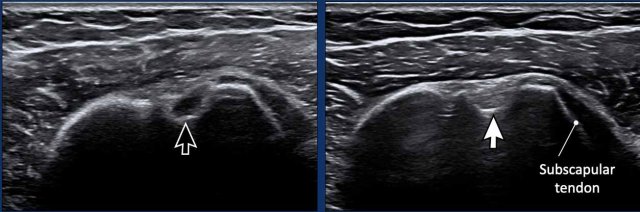

This video is of a 58-year-old female experiencing severe pain and limited movement in her shoulder.

In full external rotation, a large subcoracoid bursa  bulges over the subscapular tendon.

During endorotation a normal subscapular tendon should show almost complete passage underneath the coracoid process.

Impingement is suspected when a residual portion of the tendon is still visible during maximum endorotation.

Images

During endorotation there is incomplete passage under the coracoid and buckling of the subscapular tendon.